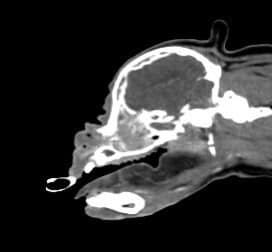

電腦斷層檢查發現左上牙齦 鼻甲骨 上顎骨到眼窩 都被侵犯